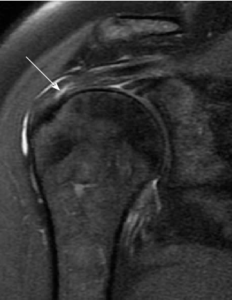

- Partial Tear : MRI may reveal a partial-thickness defect in the tendon, with some intact fibers remaining.

- Full Tear : Complete disruption of tendon fibers is evident on imaging, often creating a gap or retraction.

MRI (Magnetic Resonance Imaging)

Partial interstitial supraspinatus tendon tearMRI is a highly sensitive imaging modality for assessing soft tissue injuries, providing detailed images of the shoulder structures. Key points regarding MRI investigations include:

- Tissue Contrast : MRI can differentiate between various soft tissues, aiding in the identification of tears and their characteristics.

- Multiplanar Imaging : Enables visualization of the tear from multiple angles, enhancing diagnostic accuracy.

- Contrast Agents : In some cases, contrast agents may be used to highlight specific structures for a more detailed assessment.

- image taken from https://www .researchgate.net/ figure/ Partial-interstitial-s upraspinatus- tendon-tear-Coronal- oblique-fat-sat _fig2_ 263517775